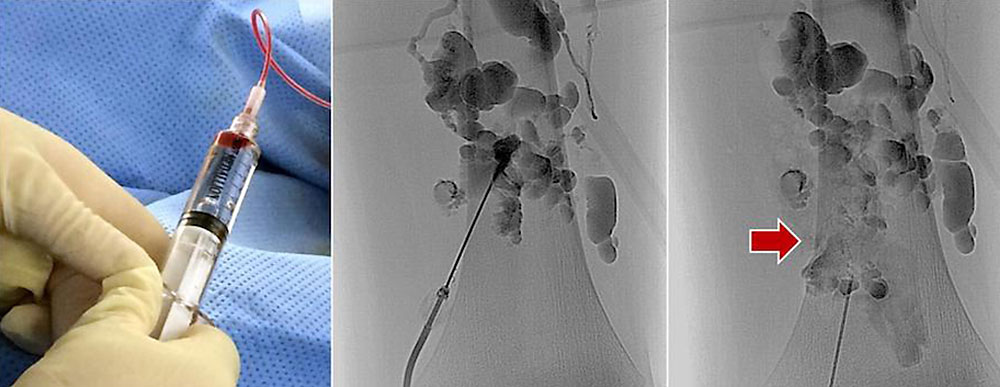

Sclerotherapy is generally performed under local anesthesia and analgosedation. In the case of sclerotherapy of the extremities, it is recommended that a tourniquet be applied during the procedure to facilitate puncture and prevent unwanted flow of sclerosing agent into the draining venous system. The vascular malformation is first punctured percutaneously by ultrasound using a needle. Depending on the size and configuration of the malformation, several punctures are often required during one treatment session.

After placement of the needle, the vascular malformation is visualized with an X-ray contrast medium (e.g., varicography). After radiographic confirmation of the correct needle position within the vessel malformation, estimation of the injection volume and exclusion of large draining vessels, the sclerosing agent is injected via the same needle. If large draining veins are visible, they should be closed before injection of the sclerosing agent. After removal of the puncture needles, a compression bandage is applied. This is important in order to allow close contact of the vein wall with the sclerosing agent and thus increase efficiency.